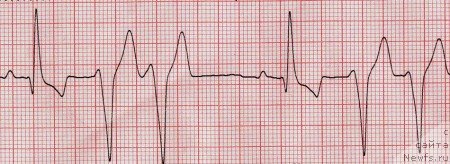

Отдельную группу составляют собаки пород доберман пинчер и боксер, у которых ДКМП протекает с длительной скрытой фазой, составляющей иногда 2-3 года. В этот период единственным отклонением от нормы является нарушение ритма сердца. У доберманов чаще всего регистрируют левожелудочковую экстрасистолию и желудочковую тахикардию (рис.5). У боксеров экстрасистолы и тахикардия имеют проавожелудочковое происхождение (рис.4).

Рис. 4. Правожелудочковая тахикардия.

Рис. 5. Парные желудочковые экстрасистолы.